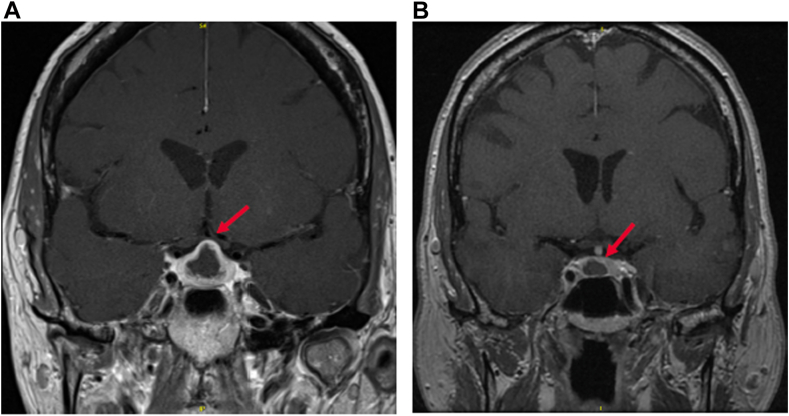

Panhypopituitarism Secondary to Pituitary Abscess